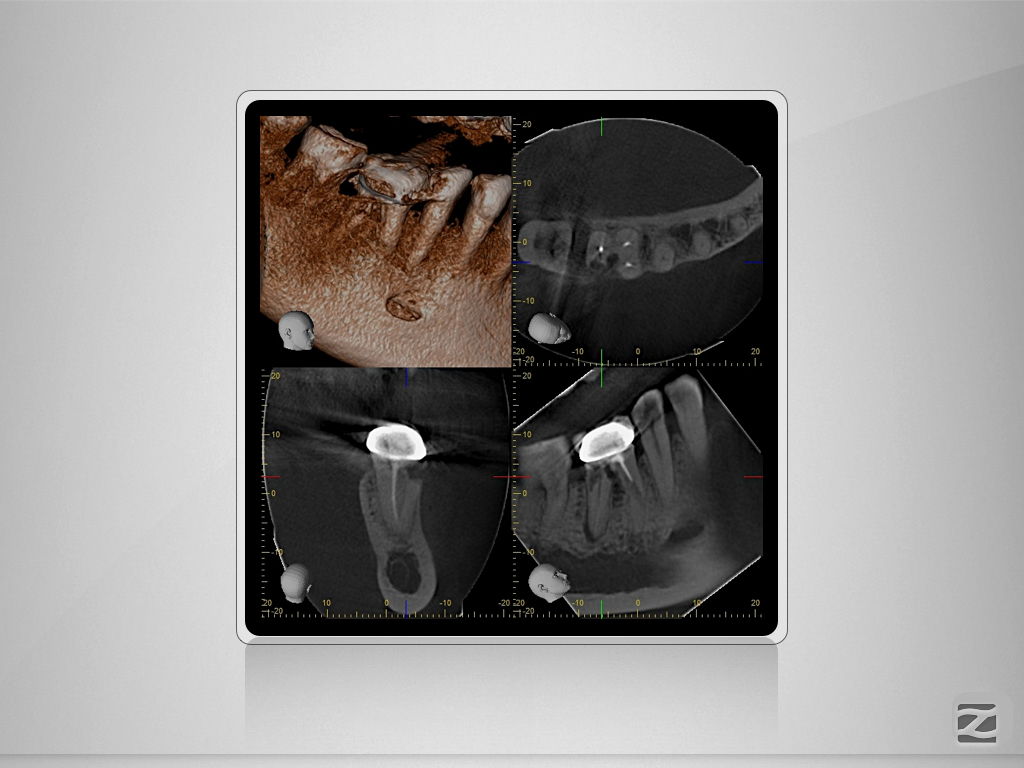

46D.009

2D vs. 3D (XXVIV)